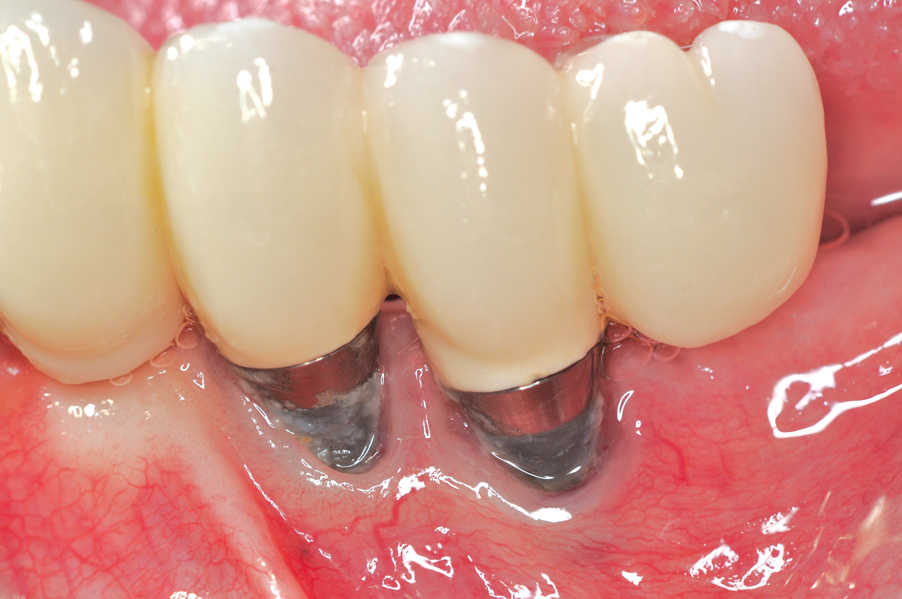

Dental implants have revolutionized the way in which clinicians treat and restore partially and fully edentulous patients and have demonstrated success for managing a broad range of clinical dilemmas. While implants have been highly predictable and have achieved long-term success, they are not immune from complications associated with improper treatment planning, poor surgical and prosthetic execution, material failure, and inadequate or infrequent maintenance. Among these problems are the biologic complications of peri-implant mucositis and peri-implantitis, which are inflammatory conditions in the soft and/or hard tissues surrounding dental implants (Figure 1 through Figure 4).1,2

Fig 5. Clinical view of implants depicting suggested bone loss. Plaque was present throughout, and the distal-most implant had substantial purulent exudate.

Figure 5

Fig 6. From a more anterior view, it was apparent that the labial positioning of these implants was outside the alveolar housing.

Figure 6